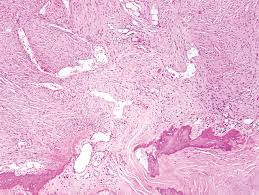

Sarcomatoid desmoplastic biphasic hmm… that looks pretty bland, but the clinician said it [s a mass. The distinction between malignant mesothelioma and reactive mesothelial proliferation can be challenging both on histology and cytology. Malignant pleural mesothelioma (mpm) is a highly aggressive and invariably fatal malignancy linked with asbestos exposure in up to 85% of cases 1, 2.more recently, germ line mutations in the bap1 gene have been identified in individuals and families with an increased prevalence of mesothelioma, uveal melanoma, epithelioid atypical spitz tumour, cutaneous melanoma and renal cell carcinoma 3, 4. Despite research efforts to develop more effective diagnostic and therapeutic approaches, malignant pleural mesothelioma (mpm) prognosis remains poor. A combination of mtap and bap1 immunohistochemistry in pleural effusion cytology for the diagnosis of mesothelioma. Hwang hc, pyott s, rodriguez s, et al. Poorer prognosis than epithelioid mesotheliomas. There was no association of gata3 labeling and bap1 status or ki67 index. At the 2020 asco annual meeting, they presented data showing that it successfully inactivated the effect of the bap1 gene mutation and provided patients with significant. In htz mice, although numerous types of cancers were developed, mesothelioma was absent or rare (2/93 htz mice) and developed after a long delay (19 and 29 months). Tumor development is associated with exposure to several known carcinogens such as asbestos fiber, rhesus virus 40, and radiation, of which asbestos exposure is the most important risk factor (2). Another issue is that most mesotheliomas of peritoneal origin do show a loss of bap1 by ihc but do not show loss of p16 by fish. The identification of molecular profiles is a powerful approach to better.

Htz germline mutations in bap1 predispose to a range of benign and malignant tumours, including mesothelioma. Gata3 and p16 are not specific to mesothelioma. Sarcomatoid desmoplastic biphasic hmm… that looks pretty bland, but the clinician said it [s a mass. The distinction between malignant mesothelioma and reactive mesothelial proliferation can be challenging both on histology and cytology. bap1 has been identified as being present in more than half of all mesothelioma tumors, as well as in a rare eye cancer known as uveal melanoma and a type of kidney cancer as well.

29, 56 biallelic bap1 gene mutations lead to bap1 loss detected by ihc, whereas monoallelic mutation does not cause bap1 loss. Malignant mesothelioma (mm) is a rare but highly aggressive neoplasm. Criteria for discrimination between fibrous pleuritis versus desmoplastic mesothelioma include evidence of neoplastic invasion for diagnosis of desmoplastic mm, but this histological assessment is. A cytokeratin stain shows that all Am j clin pathol 1998; The presence of obvious sarcomatoid areas is very helpful in establishing the diagnosis, as this variant may easily be. In their conclusion, the researchers wrote, &quot;double negativity was evident in all malignant mesotheliomas, and double positivity was observed in all. bap1 is frequently lost in epithelioid diffuse mm in contrast to sarcomatoid mesothelioma.

desmoplastic mesothelioma is another type of mesothelioma that is related to the sarcomatoid type. The most common area affected is the lining of the lungs and chest wall. Despite research efforts to develop more effective diagnostic and therapeutic approaches, malignant pleural mesothelioma (mpm) prognosis remains poor. Another issue is that most mesotheliomas of peritoneal origin do show a loss of bap1 by ihc but do not show loss of p16 by fish. The usefulness of immunohistochemistry for diagnosis of sarcomatoid mesothelioma, especially the desmoplastic. In htz mice, although numerous types of cancers were developed, mesothelioma was absent or rare (2/93 htz mice) and developed after a long delay (19 and 29 months). A histologic and immunohistochemical analysis of 31 cases including p53 immunostaining. It has a poor prognosis and a median survival time of 20 months after diagnosis ().tumor development is associated with exposure to several known carcinogens such as asbestos fiber, rhesus virus 40, and radiation, of which asbestos exposure is the most important risk factor (). Sarcomatoid desmoplastic biphasic hmm… that looks pretty bland, but the clinician said it [s a mass. For more than two years, researchers from the renowned memorial sloan kettering cancer center in new york have been studying whether the cancer drug tazemotostat could inhibit the growth of malignant mesothelioma tumors. bap1 loss in mesothelioma was originally described in the context of familial predisposition to mesothelioma in cappadocia, turkey, and the bap1 germline mutation has since been recognized as the most common germline event predisposing to pleural and peritoneal mesothelioma, particularly in young patients with no history of radiation or. Kinoshita y, hida t, hamasaki m, et al. Less commonly the lining of the abdomen and rarely the sac surrounding the heart, or the sac surrounding the testis may be affected.